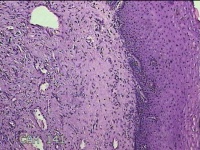

性别

女

年龄

31岁

临床诊断

宫颈上皮内瘤变

一般病史

发现宫颈CIN2 2个月。

标本名称

宫颈组织

大体所见

灰白暗红色组织2.8x1.8x0.3cm一块,表面糜烂,切面灰白暗红色,质软。

所提供图片不具有诊断价值。